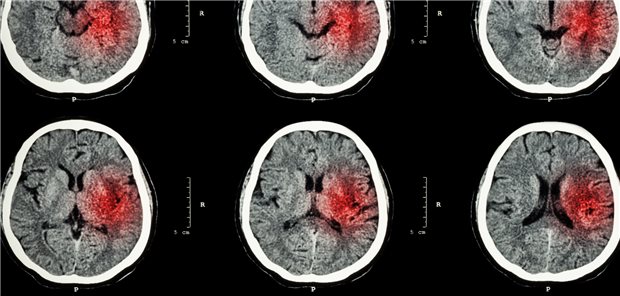

Das Risiko für Hirnblutungen nimmt unter Therapie mit Statinen nicht zu – sondern ab. Nach zehn Jahren ist es in etwa halbiert, wie eine dänische Studie ergab.